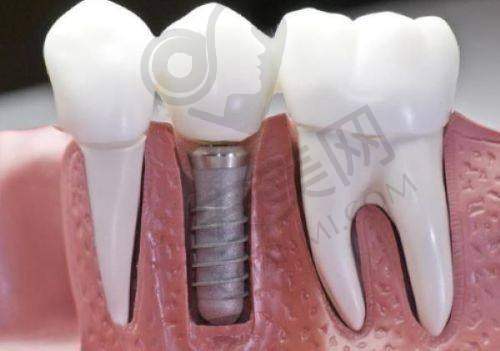

韩国维钛种植牙是一款在种植牙市场上备受关注的产品。它采用了精良的钛合金材料,这种材料具有良好的生物相容性,能够与人体牙槽骨更好地结合,提高种植牙的稳定性和成功几率。韩国维钛种植牙的表面经过特殊处理,能够促进骨细胞的生长和附着,加快种植牙与牙槽骨的愈合过程。此外,该种植牙的设计符合人体口腔生理结构,能够更好地修复牙齿的咀嚼功能和美观度。它的外观与真牙相似,几乎可以达到以假乱真的成效,让患者在修复口腔功能的同时,也能拥有自信的笑容。